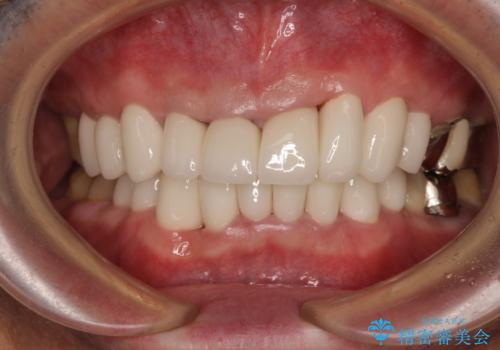

上下ともに前歯のセラミッククラウンによる補綴治療を希望されていましたが、下顎前歯は叢生が強いため、補綴治療前に部分矯正を行って歯列を整えた上で、補綴治療を行うこととしました。

臼歯部には歯周ポケットのある箇所が散見されましたが、まずは前歯を治療したいとのことで、治療を進めました。

ディープバイトにより臼歯部に負担のかかる咬合であったので、補綴治療後には、矯正治療の後戻り防止もかねて、睡眠時にマウスピースを装着するように指示しました。